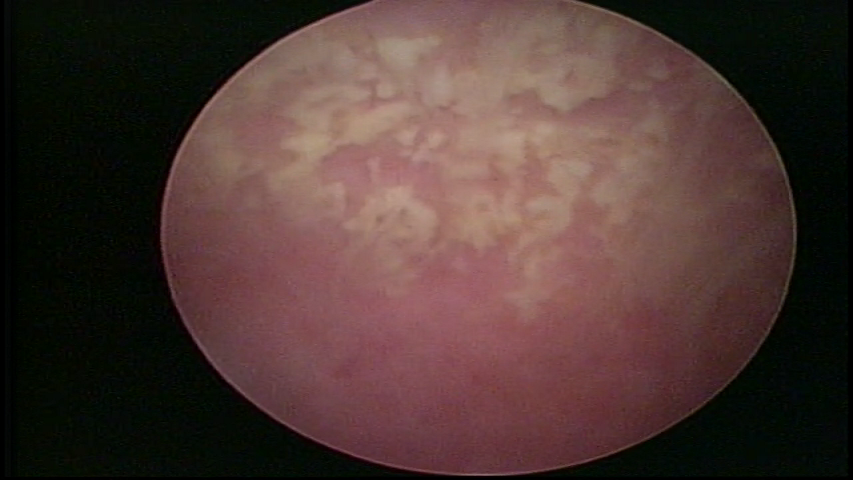

ACUTE ENDOMETRITIS

In video hysteroscopy, we observe the endometrium bleeding, its endometrial surface is speckled, presenting a “creamy” aspect and a whitish color with a brightness enhanced by the fibrin accumulated. Bluish or rough areas, which may correspond to cystic necrosis. The presence of adhering mucus or pyometra may occur.